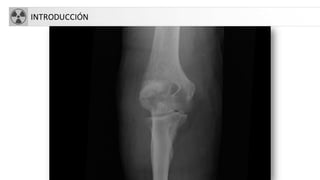

INTRODUCCIÓN

• Rx simple: primera exploración a realizar

• Antecedentesy valoración clínica: edad,

localización,síntomas, tiempo evolución…

• Aspectos técnicos:

– 2 proyecciones: AP y lateral (90º una de otra)

– Incluir 2 articulaciones adyacentes

– 2 miembros(imágenes comparativas)

– 2 exploraciones sucesivas para ver evolución